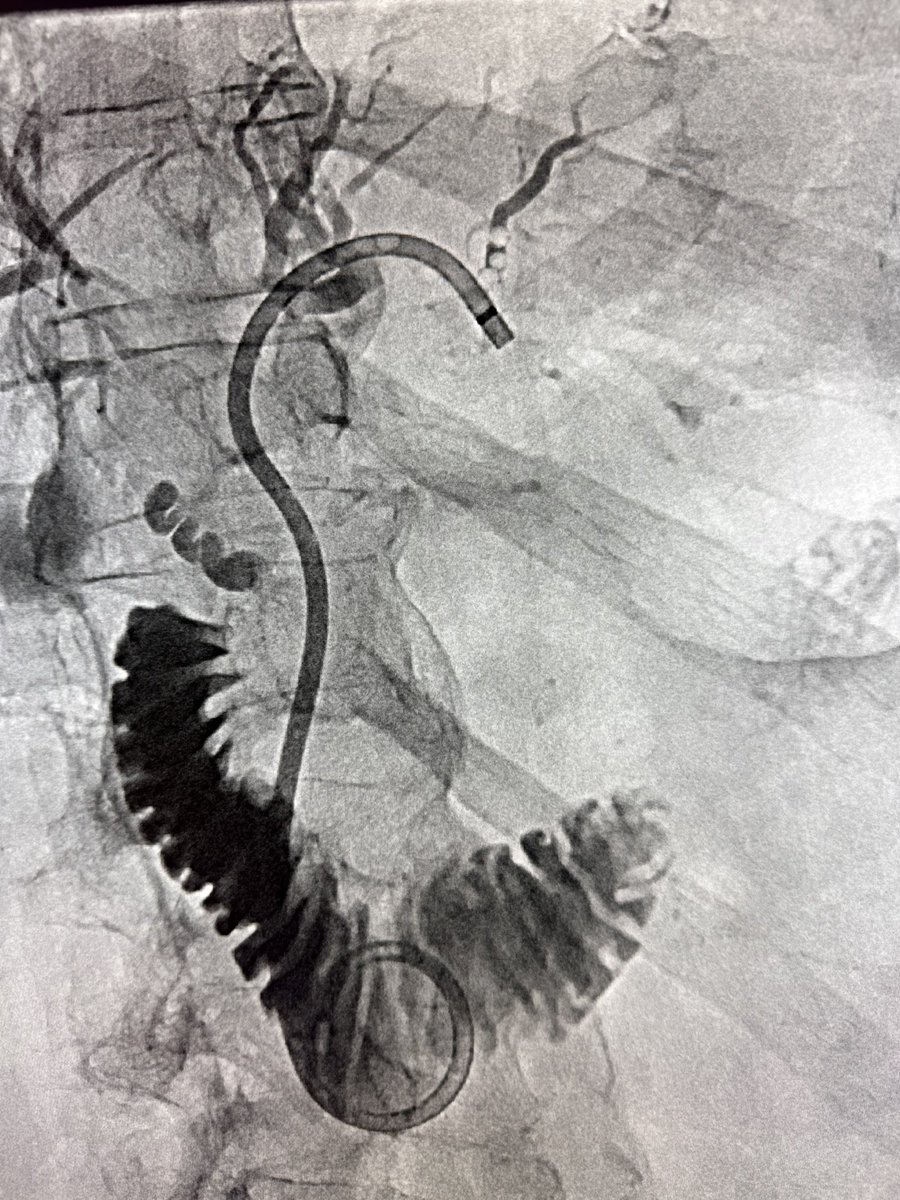

Looks like lead! But it isn’t! Equivalent radiation protection with barium sulfate, bismuth oxide impregnated fabric. Lighter washable why didn’t I know bout this?